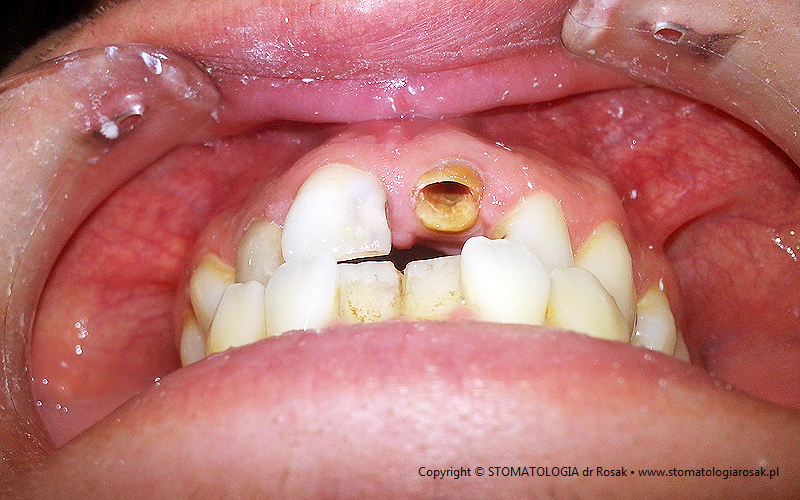

12. Pacjent zgłosił się celem usunięcia zniszczonego korzenia zęba jedynki. Zdecydowano się uratować korzeń !!!

| 12a. Pacjent przed leczeniem |

12b. Zacementowano rusztowanie stanowiące podporę dla przyszłej korony tzw. wkład koronowo-korzeniowy |

| 12c. Gotowy wkład koronowo-korzeniowy lany |

12d. Gotowa korona porcelanowa na metalu |